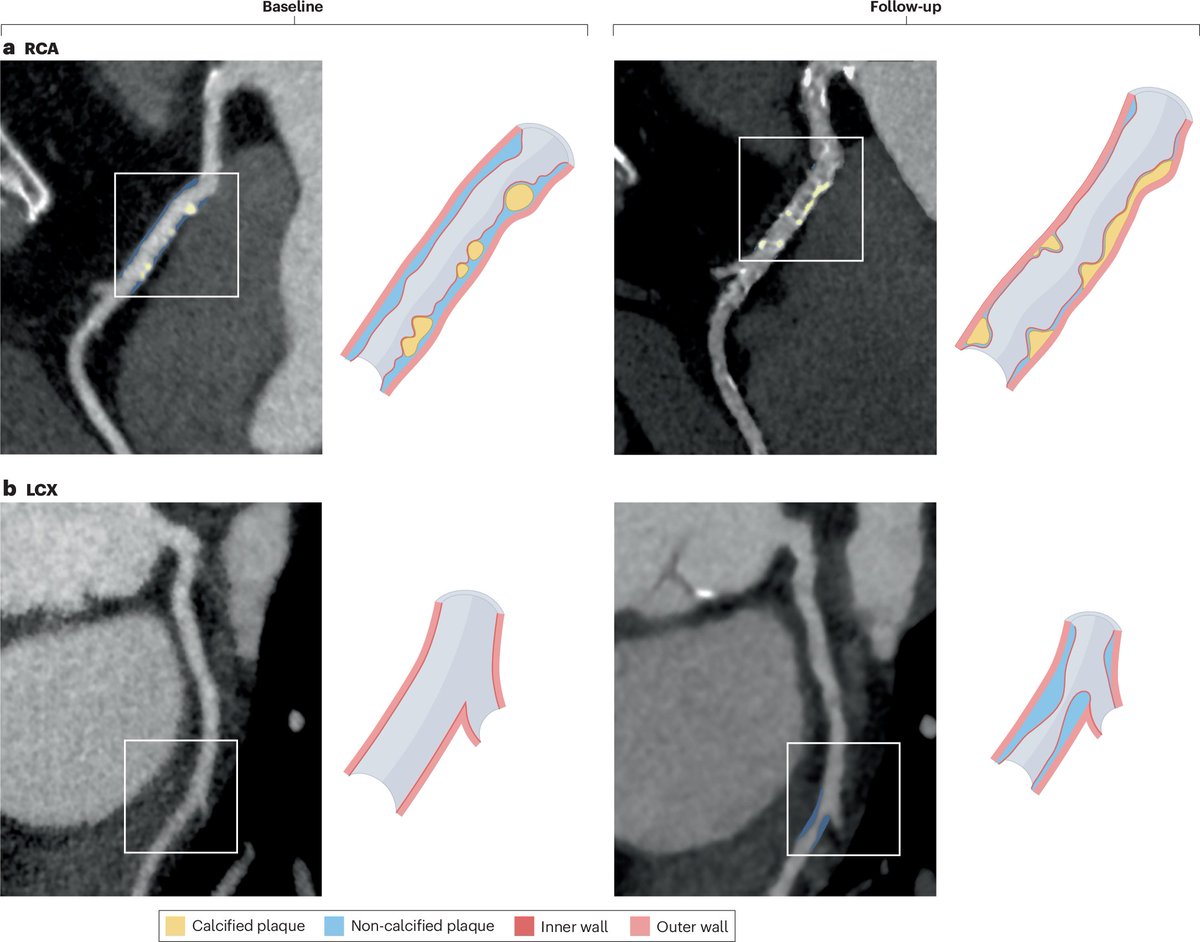

Aged garlic was shown to shrink arterial plaques in a landmark clinical trial.

(🧵1/7)Image

This study was published in 2019, examining people with diabetes with plaque in the coronary artery.

This is the primary place where if plaque forms, you're susceptible to a heart attack. Image

They also used what is now considered the best tool for predicting heart disease - Coronary Computed Tomography Angiography (CCTA).

This is an imaging technique used to visualize the plaques.

For this reason, it's incredibly accurate at seeing active disease. Image